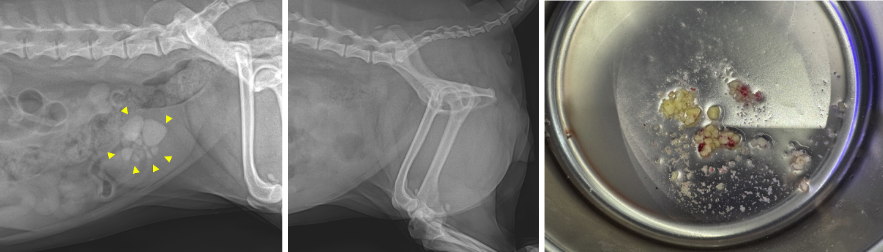

양산·부산 강아지 방광결석 수술 전(좌) / 수술 후 (중) / 레이져 파쇄로 조각나 있는 결석들(우) / 출처: 에스동물메디컬센터 양산점

03 수술 결과

무절개 결석 제거 수술 후 시행한 초음파에서 방광 내 결석이 모두 제거된 상태가 확인되었습니다. 이후에도 에스동물메디컬센터 의료진이 세심하게 모니터링하며 입원 치료를 이어갔고, 전반적인 컨디션이 충분히 안정된 것을 확인한 뒤 안전하게 퇴원하였습니다.

강아지 무절개 결석제거 수술 후 방광 초음파 영상 (결석 없음) / 출처: 에스동물메디컬센터 양산점